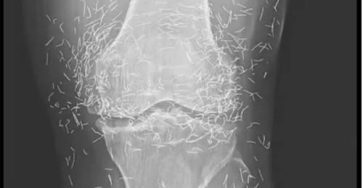

🩻 X-Ray Reveals Gold Acupuncture Needles in Woman’s Knees – What Really Happened

When doctors examined the X-ray of a 65-year-old woman in South Korea with severe knee pain, they didn’t just see…